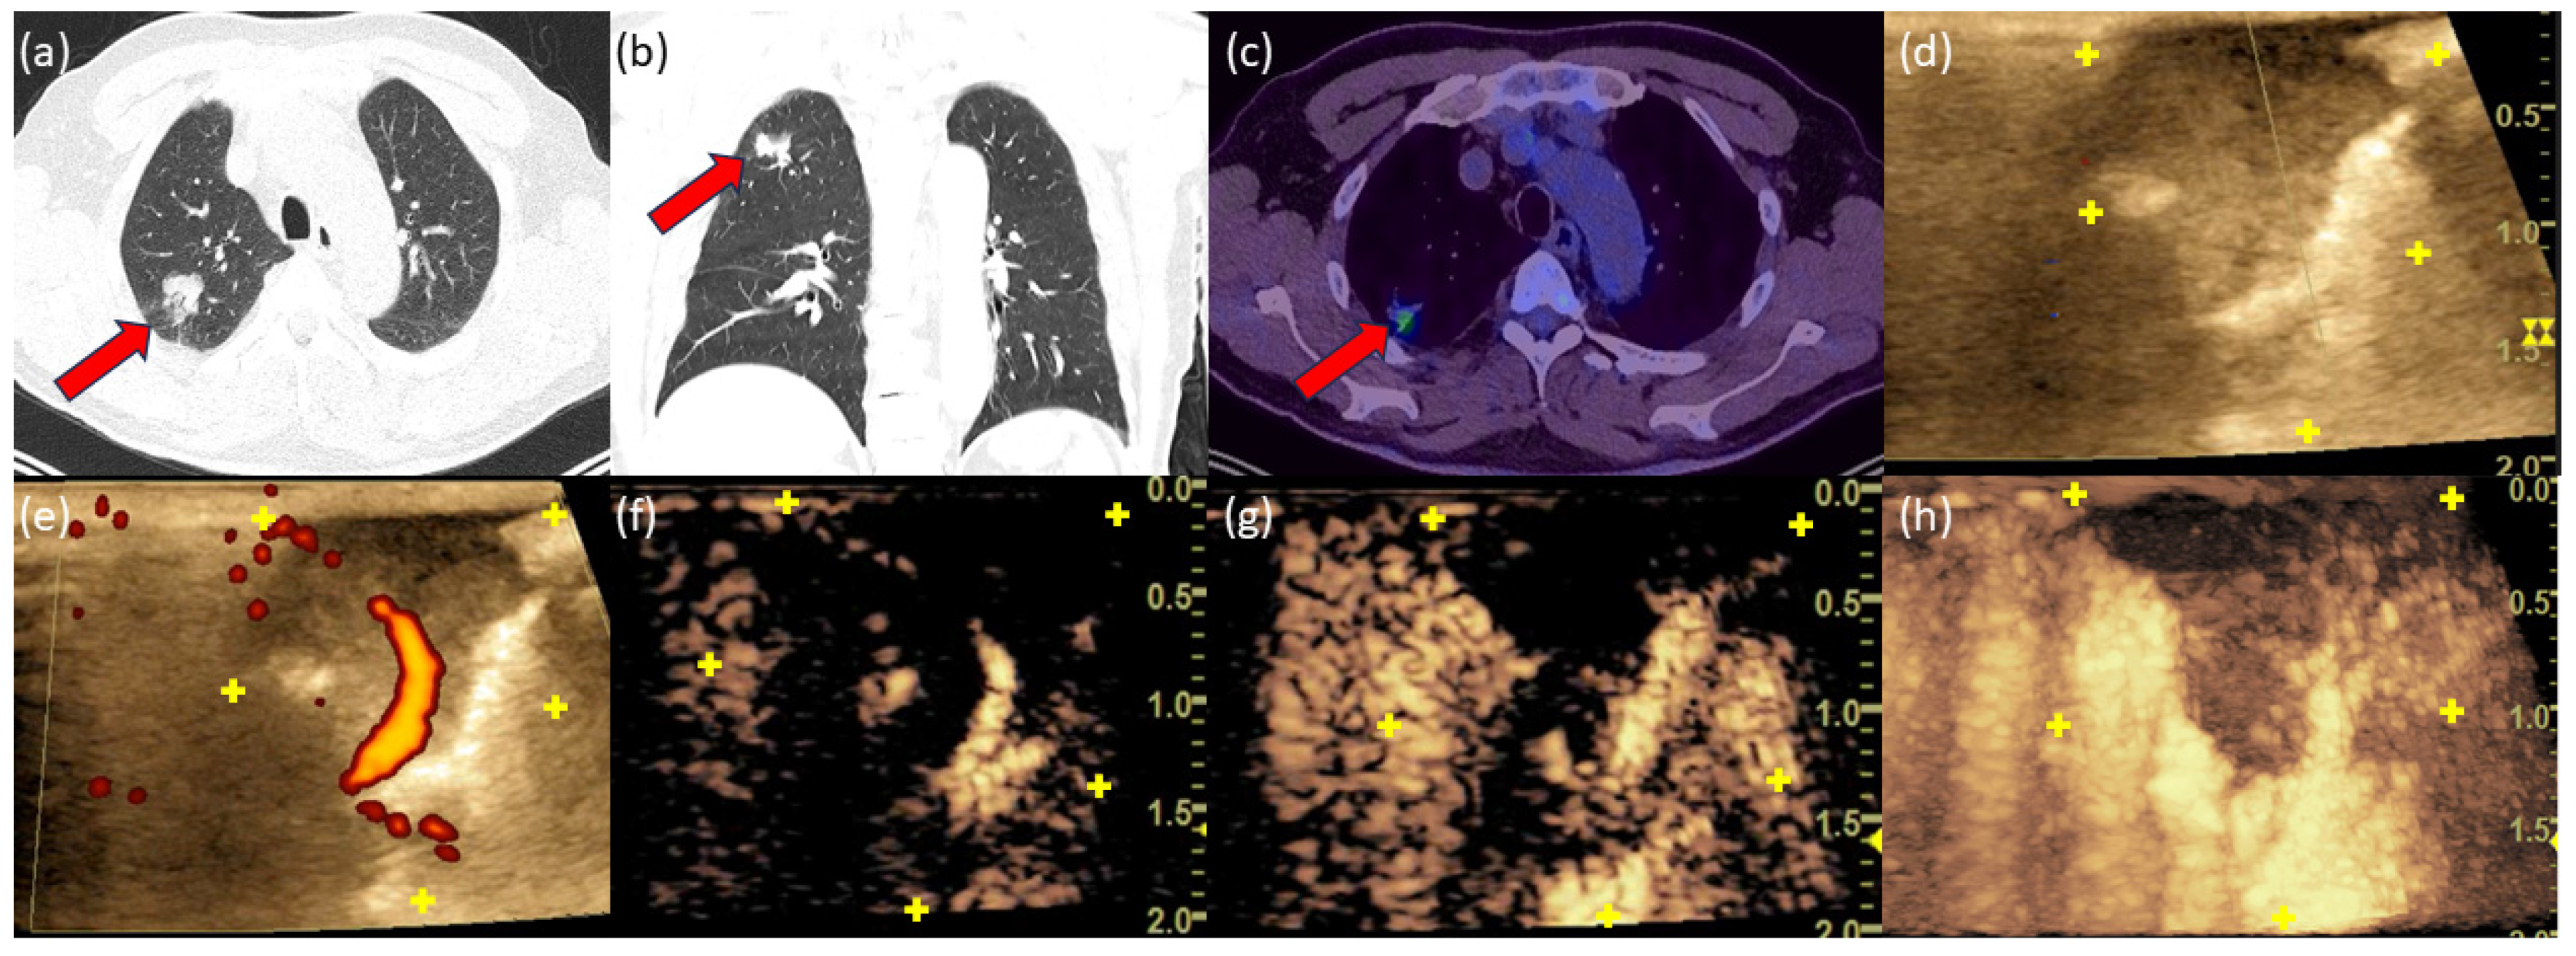

3.5. Case 1